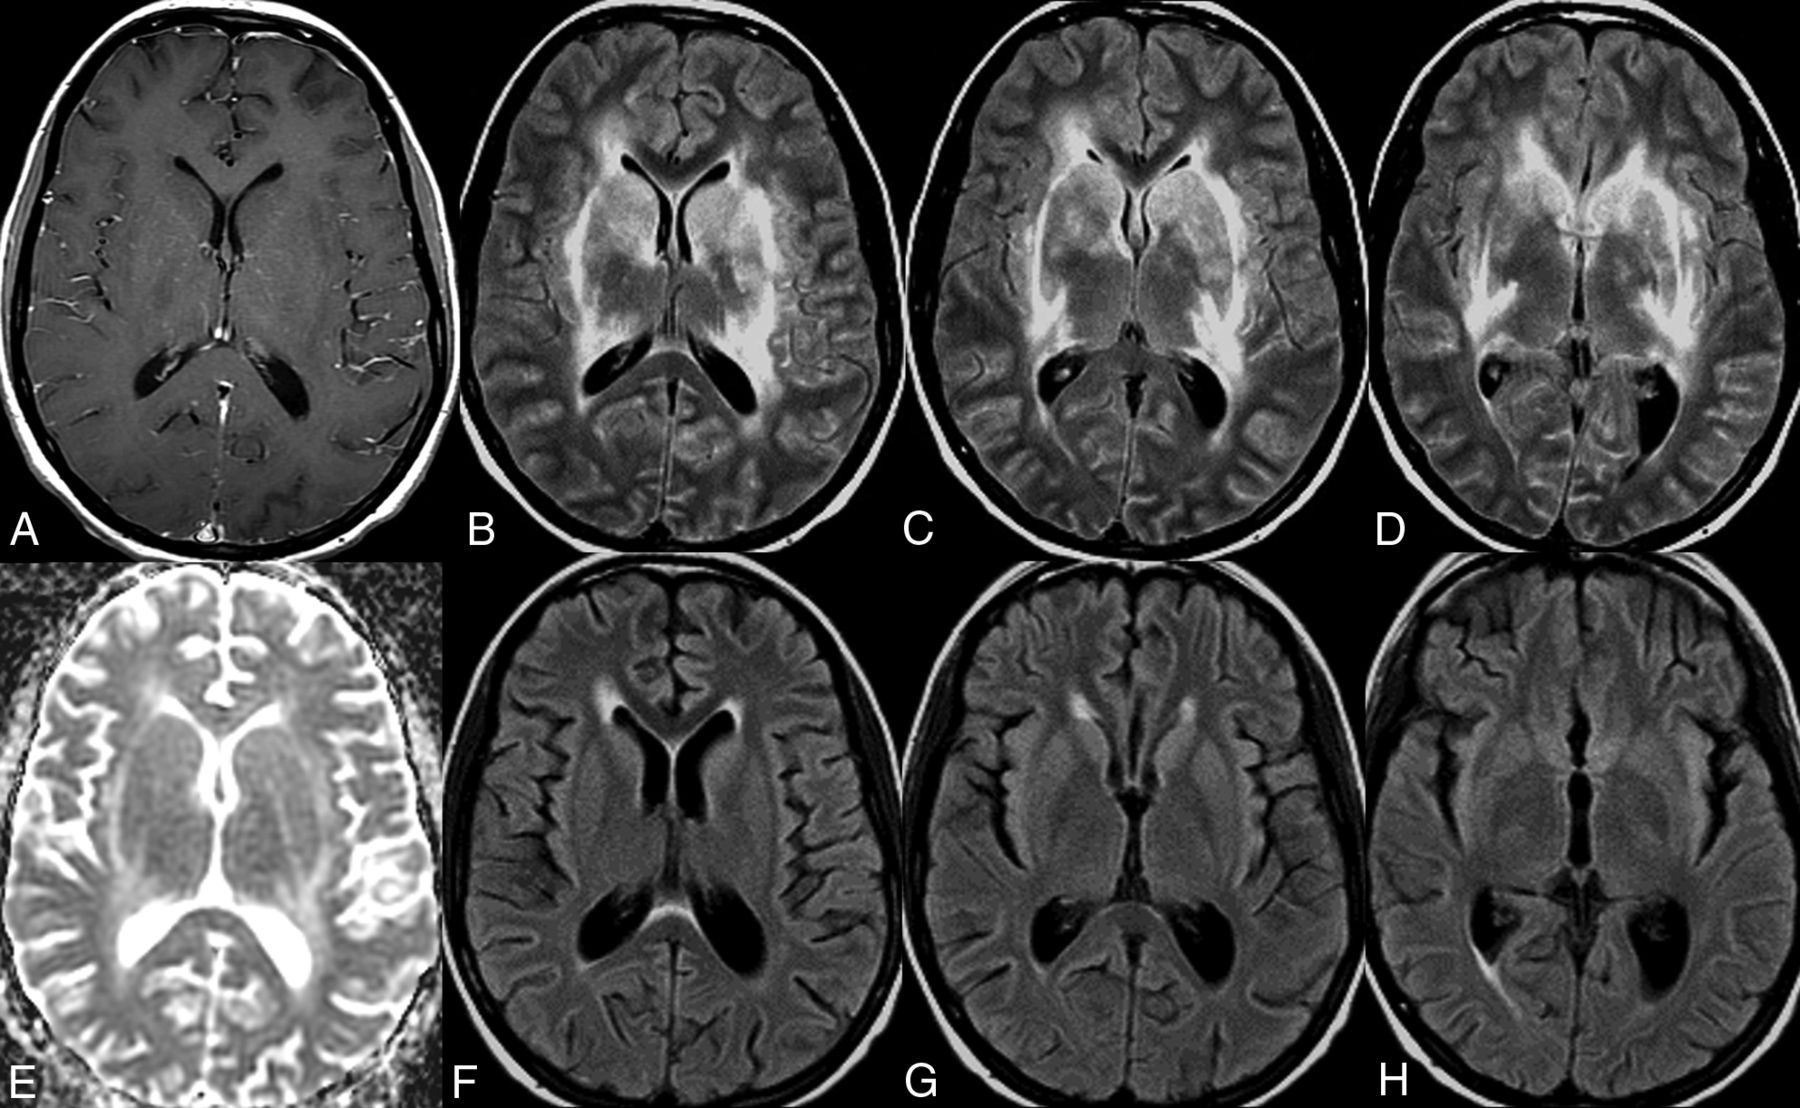

A 68-year-old woman with a medical history of rheumatoid arthritis, SLE, and type 2 diabetes mellitus presented with cognitive decline and generalized weakness. MR imaging of the brain demonstrated bilateral symmetric T2/FLAIR hyperintensity of the basal ganglia, thalami, and surrounding white matter without restricted diffusion or postcontrast enhancement (Fig 1A–E). An IV steroid regimen was attempted twice (methylprednisolone on both occasions) but was discontinued due to the complication of gastrointestinal bleeding. She was ultimately given the clinical diagnosis of autoimmune encephalitis and received 5 sessions of plasmapheresis with prompt clinical and radiologic improvement. Follow-up MR imaging of the brain demonstrated near-complete resolution of the previous T2/FLAIR signal abnormality (Fig 1F–H).

Neuropsychiatric lupus with antibody-mediated striatal encephalitis. A 68-year-old woman with a medical history of rheumatoid arthritis, systemic lupus erythematosus, type 2 diabetes mellitus, and hypertension presents with cognitive decline and generalized weakness. MR imaging of the brain demonstrates bilateral symmetric T2/FLAIR hyperintensity of the basal ganglia, thalami, and surrounding white matter (B–D) without restricted diffusion (E) or postcontrast enhancement (A). An IV steroid regimen was initiated but stopped due to gastrointestinal bleeding, and the patient received 5 rounds of plasmapheresis with a positive clinical response. Follow-up MR imaging of the brain demonstrates near-complete resolution of previous T2/FLAIR signal abnormality (F–H).